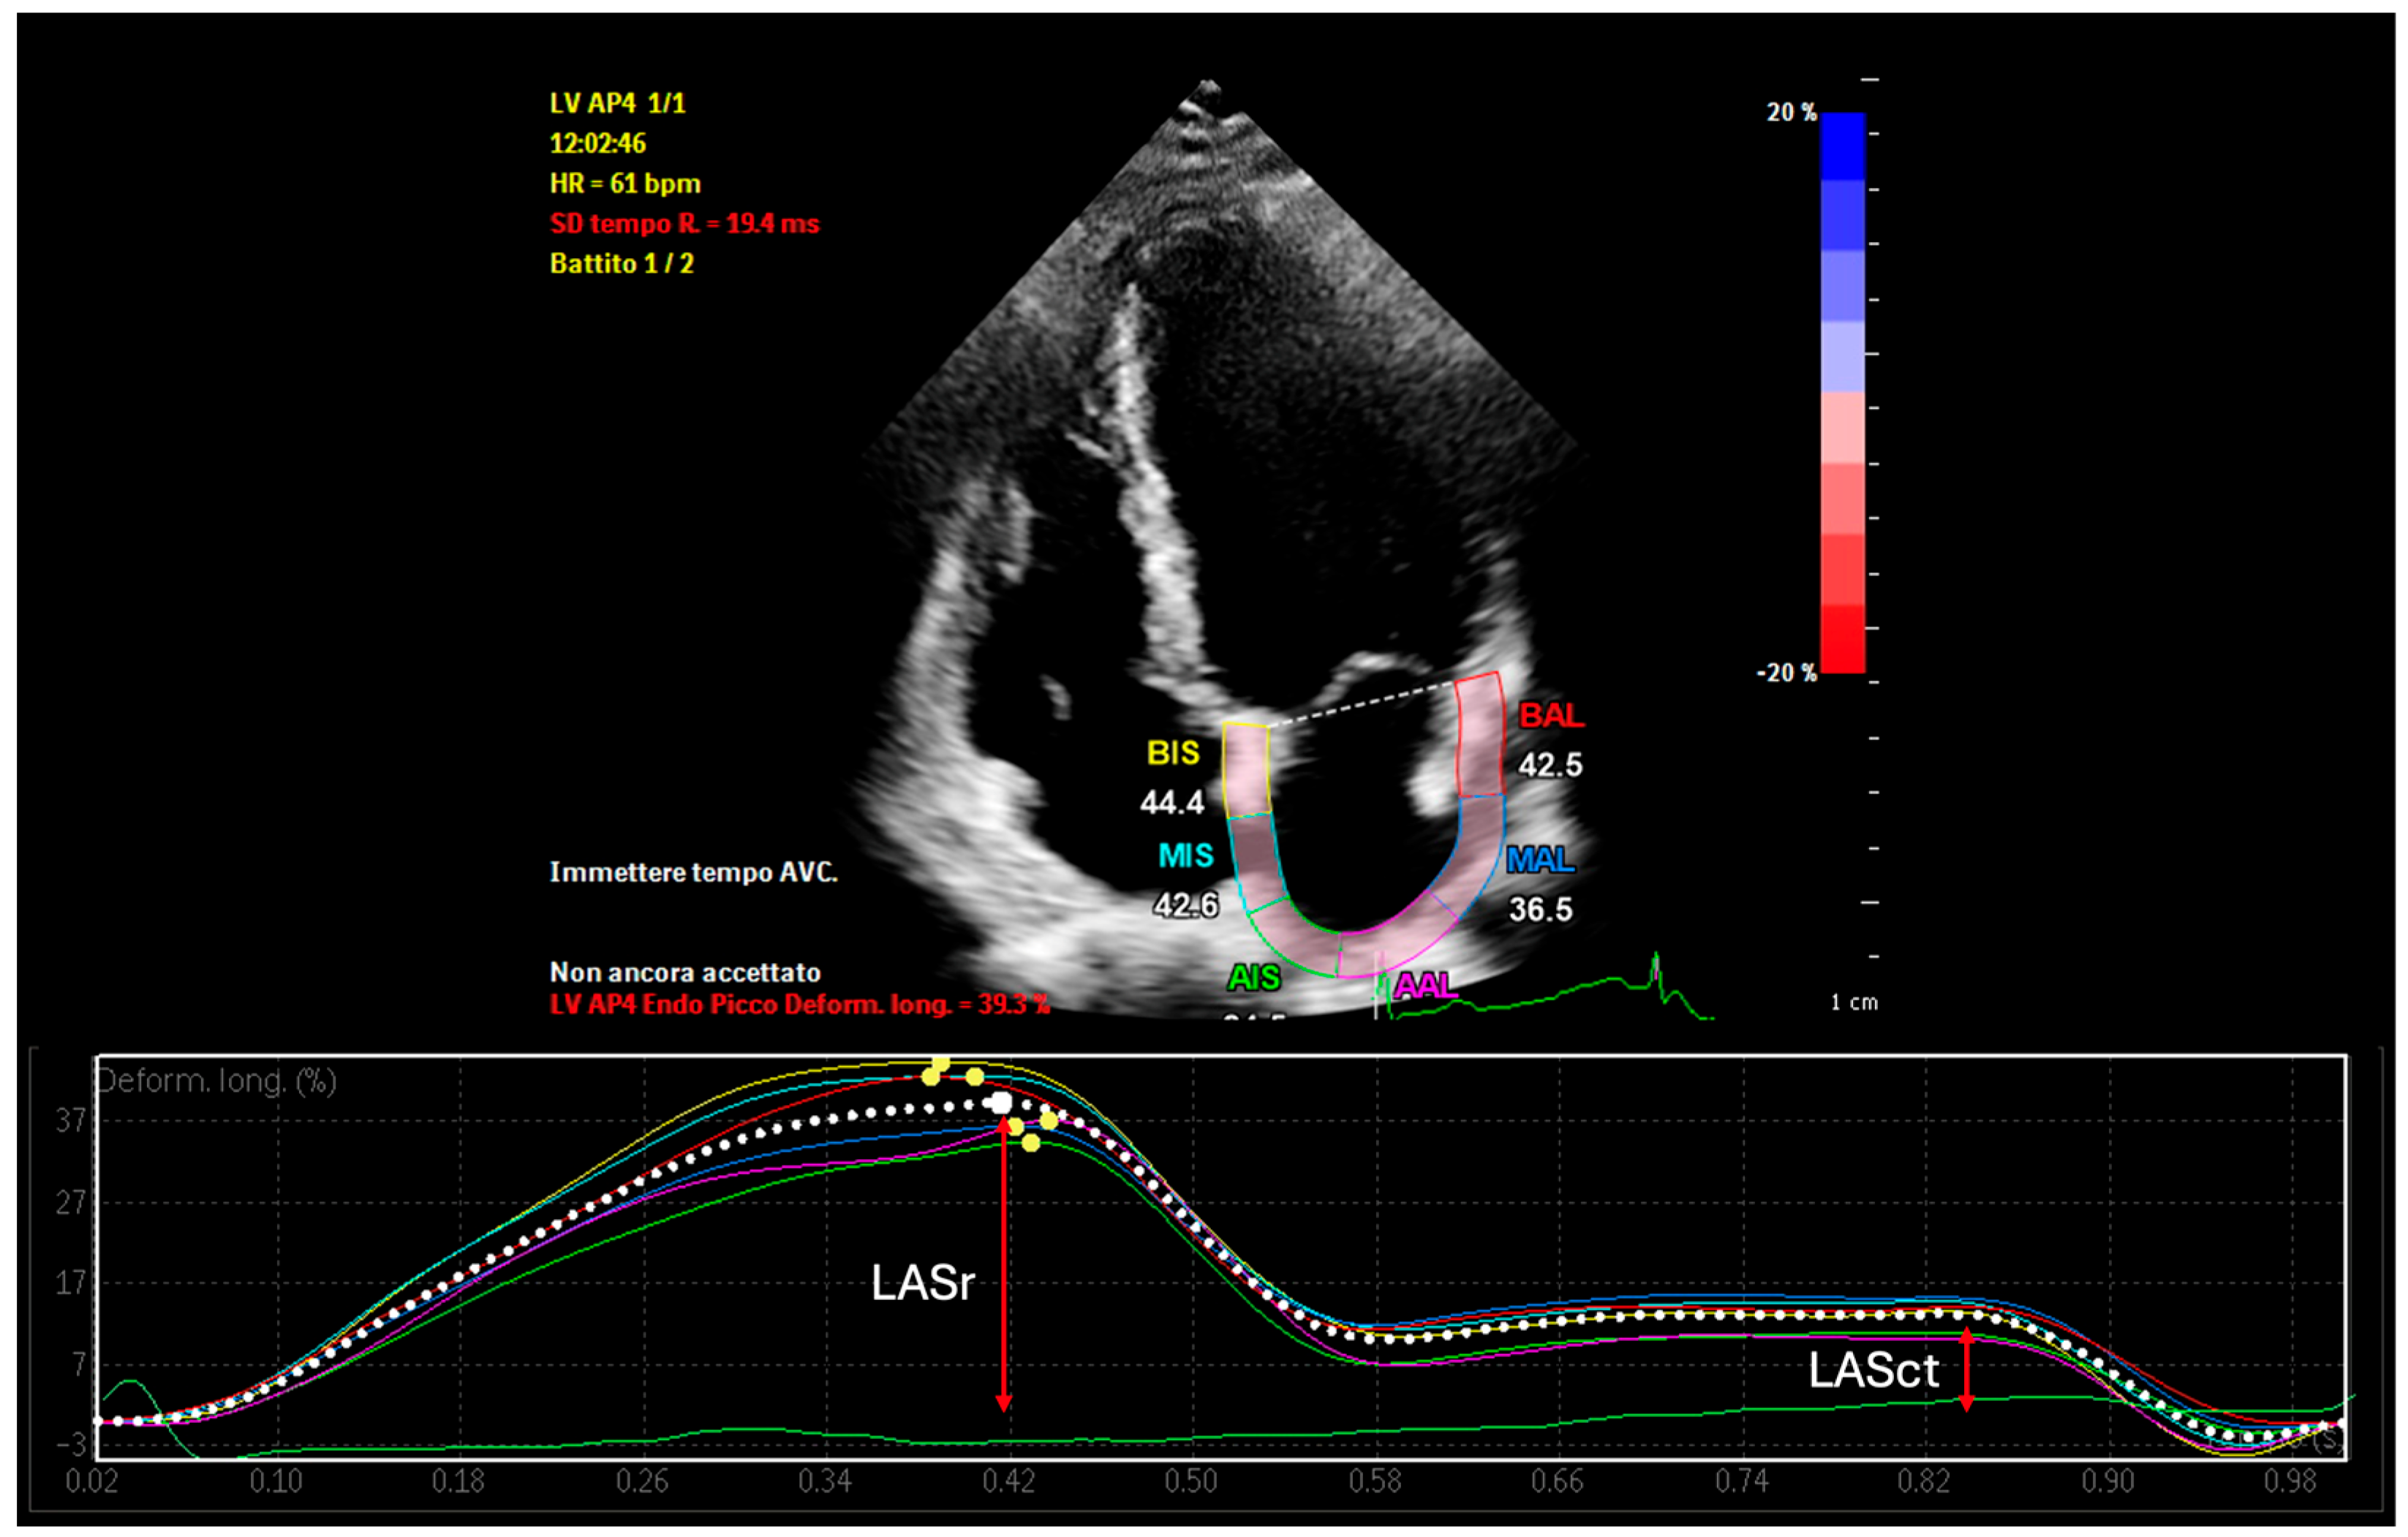

| LASr | Left Atrial Reservoir Strain |

| LASct | Left Atrial Contractile Strain |

| LASr (Reservoir Strain) | Reflects LA compliance and fibrosis; lower values indicate impaired reservoir function | Corresponds to low-voltage zones (<0.5 mV), reduced CFAE density, and fibrotic substrate |

| LASct (Contractile Strain) | Reflects active LA contraction; low values indicate poor contractile function | Predictive of atrial standstill, late potentials loss, and reduced sinus rhythm maintenance post-ablation |